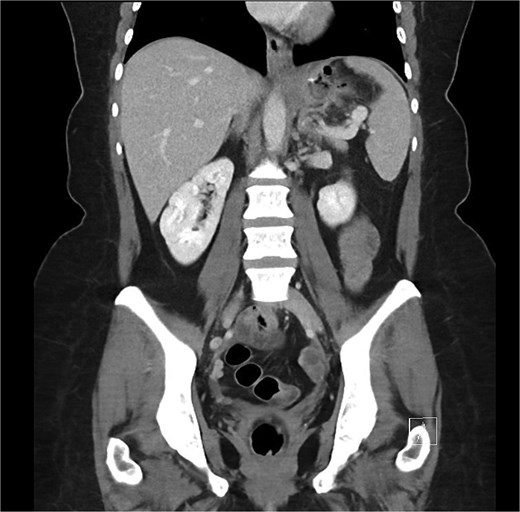

A 46-year-old female underwent an uncomplicated LSG for weight loss. Four weeks post-operatively she represented with epigastric pain and was diagnosed with an acute, contained leak on computed tomography (CT) (Fig. 1). The patient at the time was systemically well with a normal white cell count (WCC) and a C-reactive protein (CRP) of 67. Given this, a conservative approach was proposed with endoscopic internal drainage using double pigtail stents in conjunction with nasojejunal (NJ) feeds, and/or endoscopic negative pressure vacuum therapy. However, the patient was not willing to pursue enteral feeding or internal drainage and ultimately opted for primary closure of the defect endoscopically which was performed using argon beam coagulation and two X-tack suture devices.

Coronal portal venous phase CT scan of the abdomen and pelvis demonstrating the proximal gastric leak with extra-luminal air in the gastrosplenic ligament.